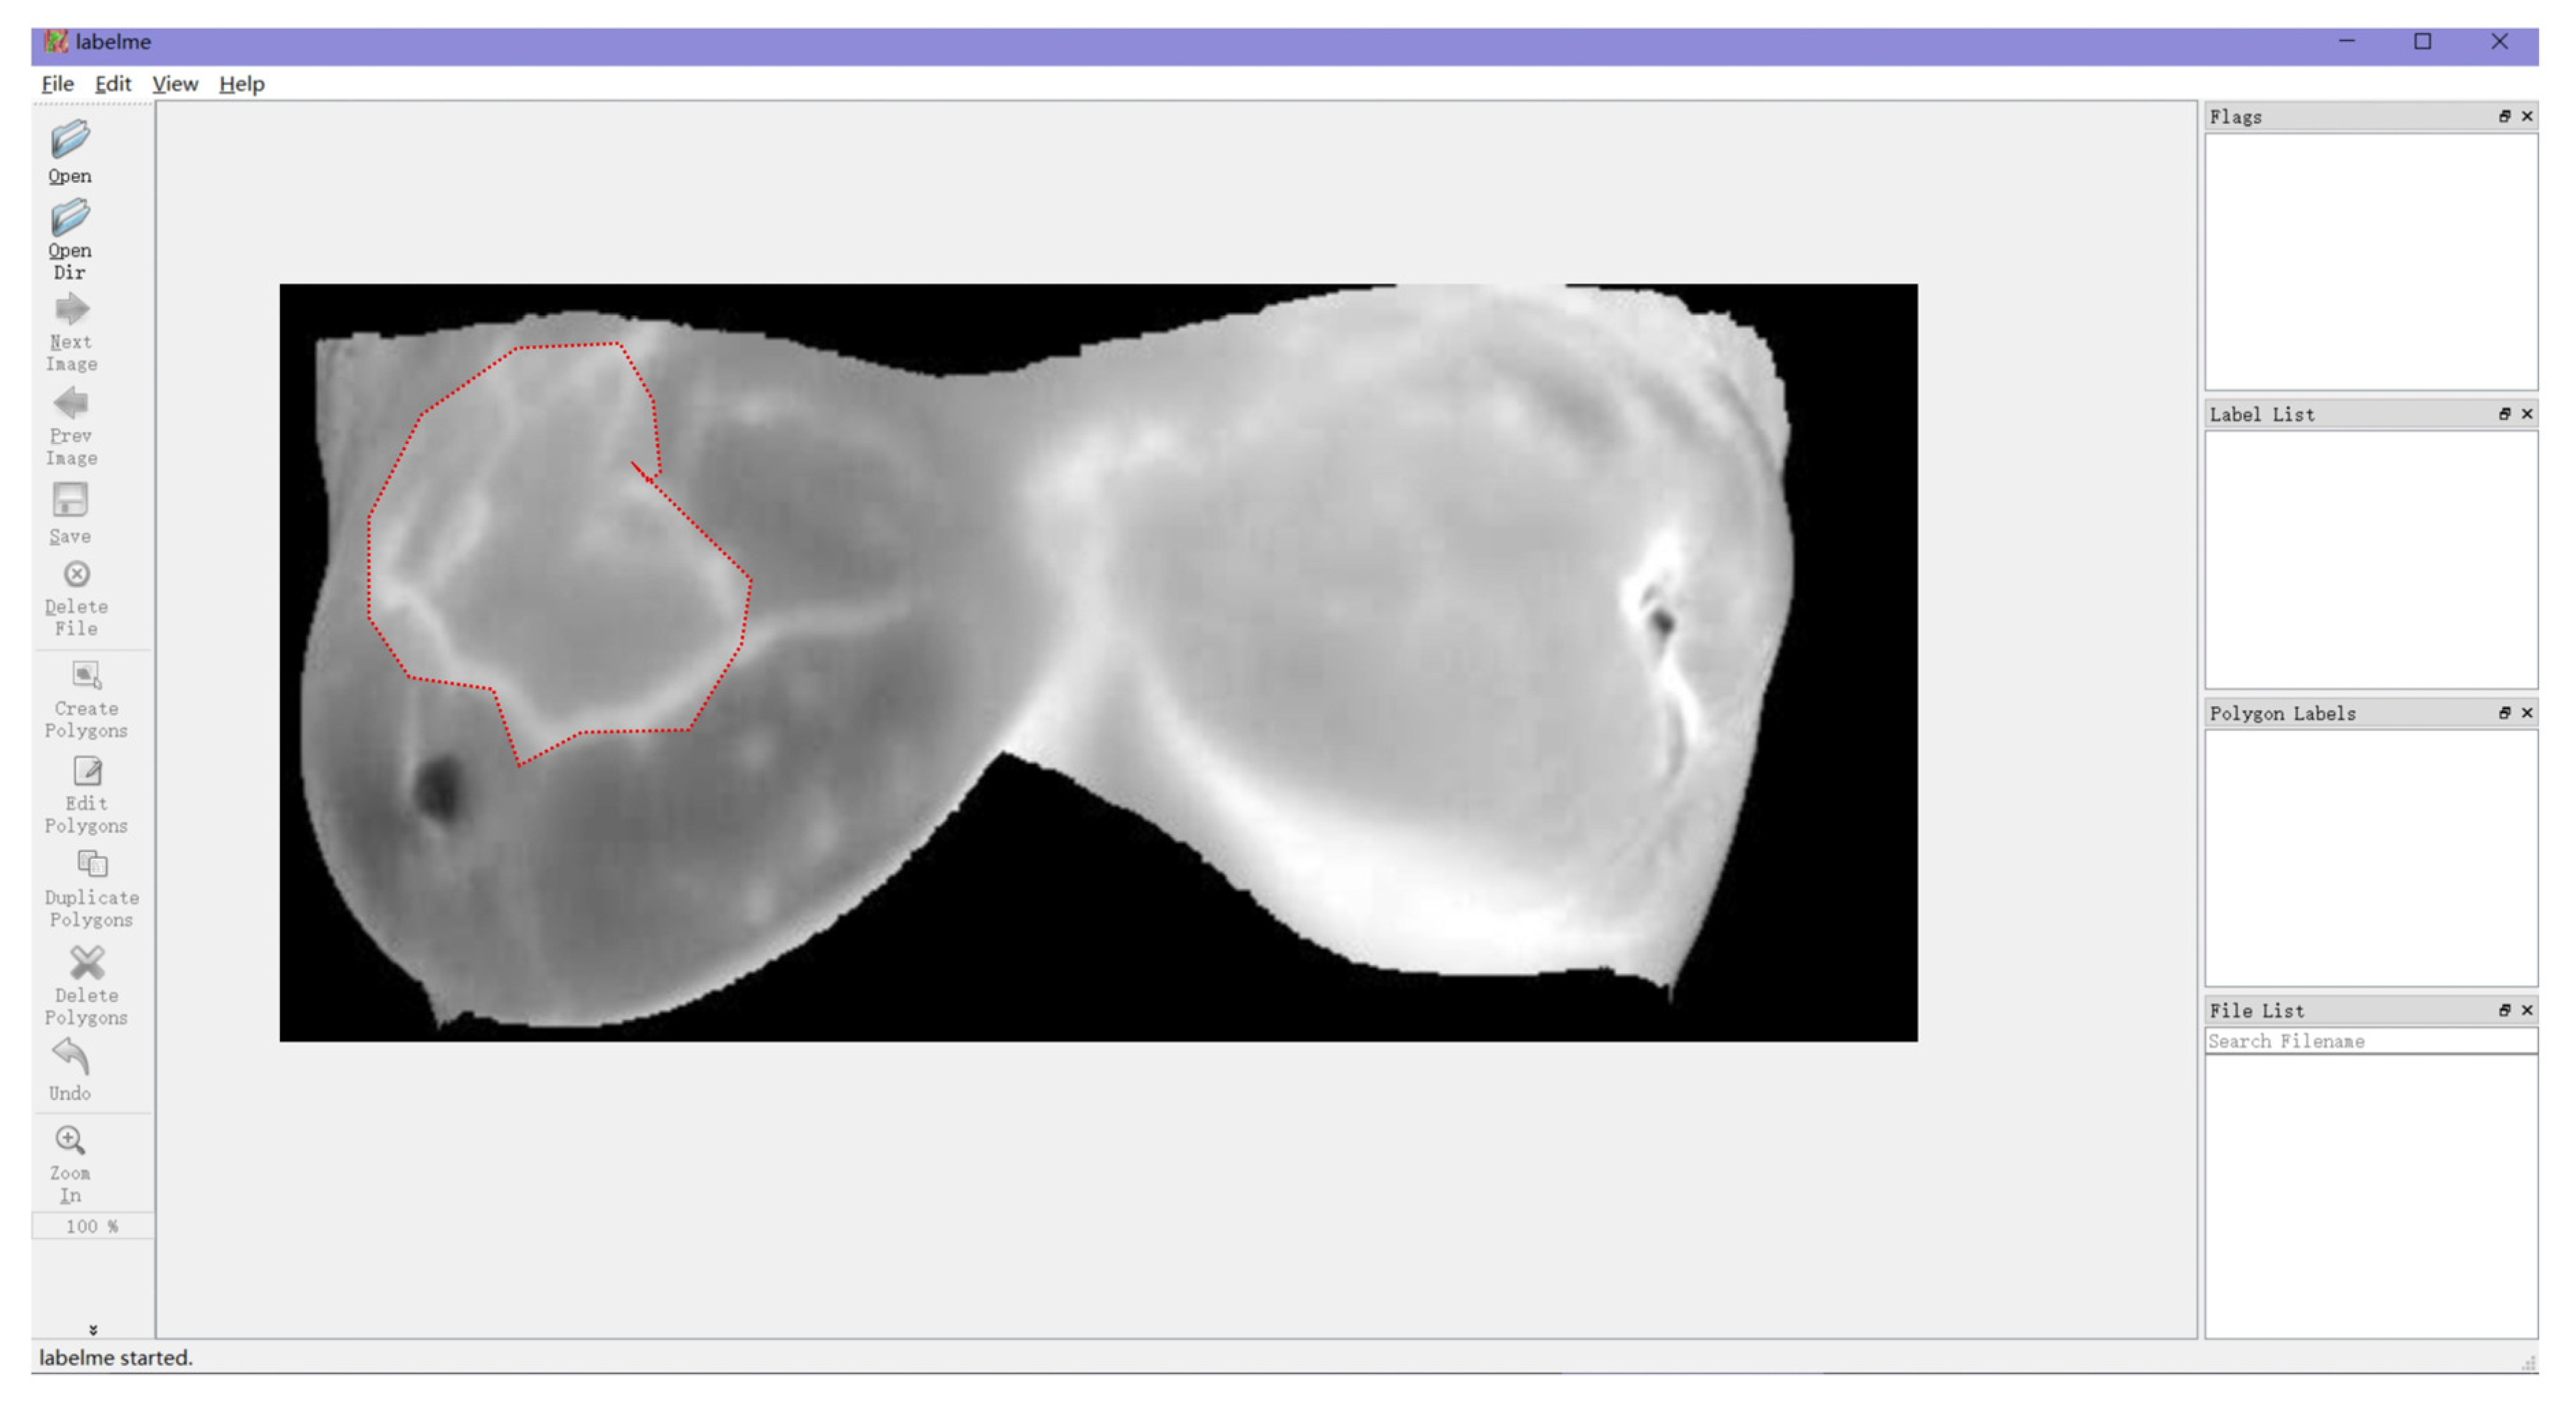

2.4. Database Construction and Data Preprocessing